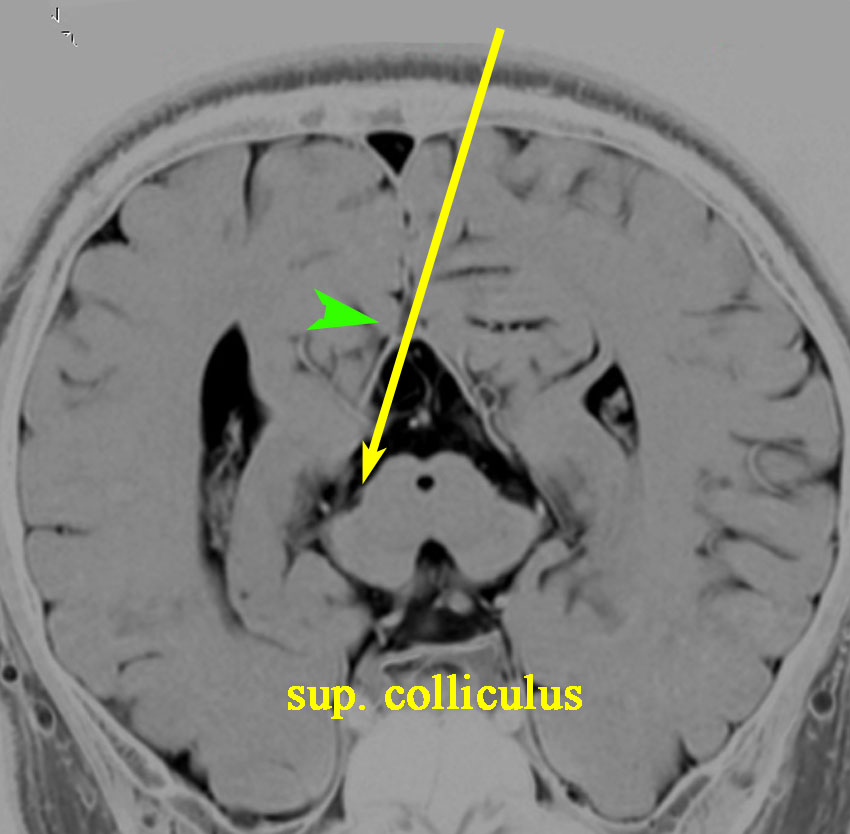

5. 後交連 PC posterior commissure

松果体腫瘍が上丘を圧迫して眼球運動障害を呈することは良く知られています。実際に松果体腫瘍の手術で上丘を損傷することはほとんどなく,術後に残る微妙な複視は,後交連 (PC posterior commissure) の損傷によって生じます。左の画像のように,松果体腫瘍が第3脳室方向に伸展増大すると後交連を圧排して,後交連は扁平化します。手術中には,上丘の奥に,上丘と連続して白く薄い脆弱な白質組織が見えます。それが後交連です。左右にも長い白質組織なので,腫瘍底面から非常に慎重に剥離する必要があります。後交連の剥離が終わると第3脳室内の髄液腔に抜けます。